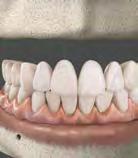

–Corticotomías y Ortodoncia. Ampliando límites del movimiento dental, por la Dra. Aranzazu Senosiain y cols. [50]